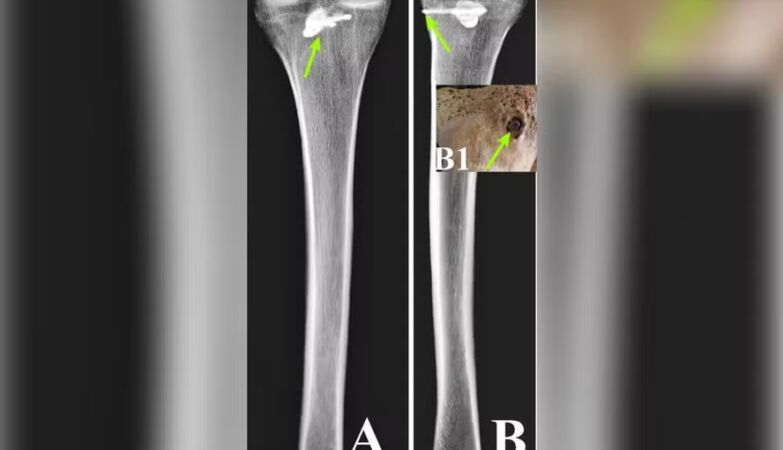

Examinations with fluorescent X-rays and computerized tomography confirmed that it was a three-bladed arrow, approximately 44 millimeters long and 15 millimeters wide, typical of Parthian armory, describes the .

The bone around the object showed signs of healing, indicating that the man survived for some time after impact, although it is not possible to determine for how long.